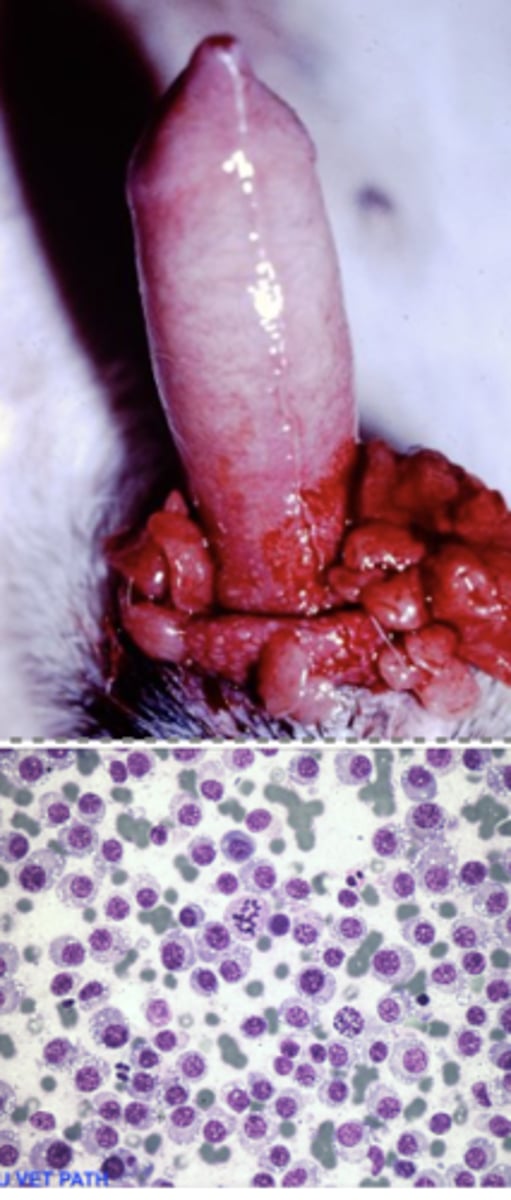

Transmissible Venereal Tumor (TVT)

-TRANSMISSIBLE tumor thru direct contact

What kind of round cell tumor is this?